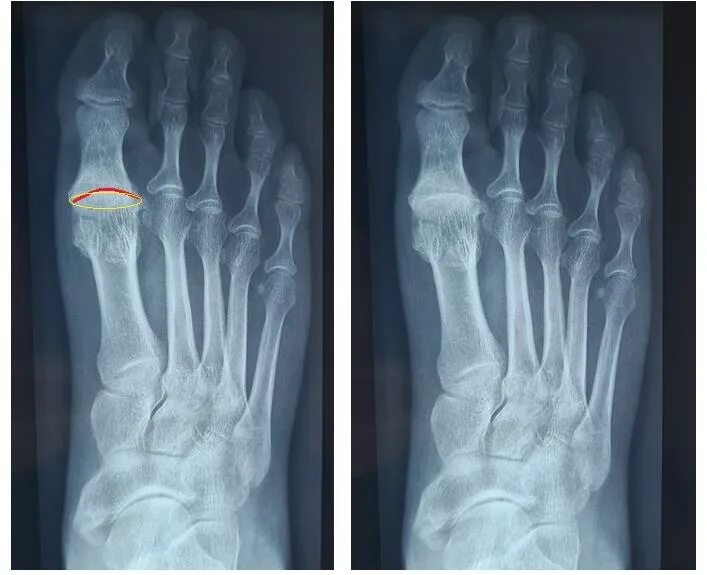

Артроз 1 степени плюснефалангового сустава стопы